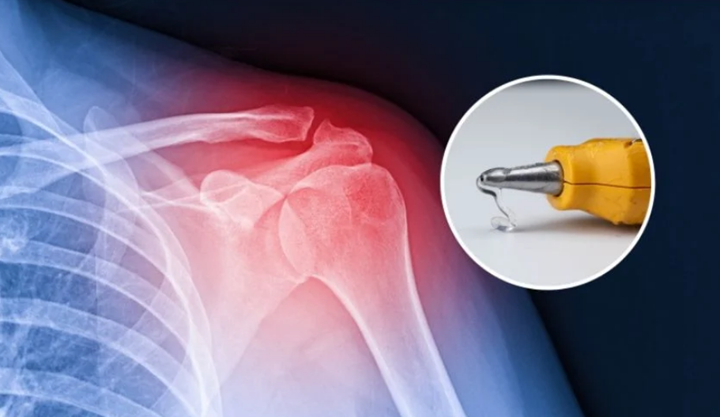

利用3D打印技術(shù)修復(fù)骨骼

你知道嗎?用于填補(bǔ)骨骼孔洞的醫(yī)用膠水不僅不環(huán)保,而且還可能引發(fā)嚴(yán)重的炎癥風(fēng)險(xiǎn)。韓國成均館大學(xué)(SKKU)的研究人員開發(fā)了一種更巧妙的骨骼修復(fù)技術(shù)——利用3D打印技術(shù)。這項(xiàng)技術(shù)需要一種經(jīng)過改進(jìn)的膠槍,能夠在手術(shù)過程中將骨移植物直接打印到活體組織上。